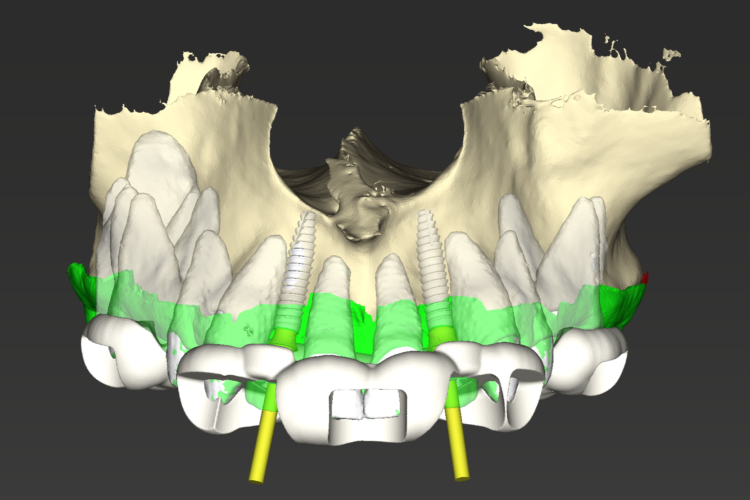

Pre-surgical workup (December 2022)

After completing orthodontic treatment, the patient attended a workup appointment, which included a CT scan, intraoral scans and pre-surgical photos and measurements.

The implant surgery was performed in May 2023 and was filmed live as part of a surgical demonstration for the delegates on a guided surgery course being run by the Fitz Fahey Academy. Implants were placed in the UR2 and UL2 spaces with simultaneous hard and soft tissue grafting. Following the surgery, the patient was provided temporary teeth and instructed to avoid putting undue pressure on the implants during healing.